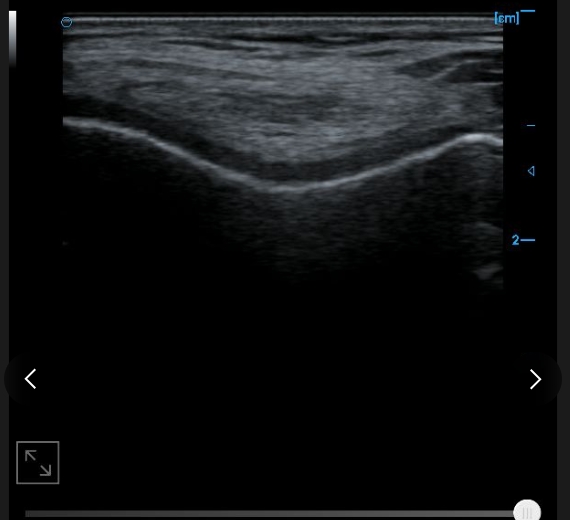

Patellar tendon B image